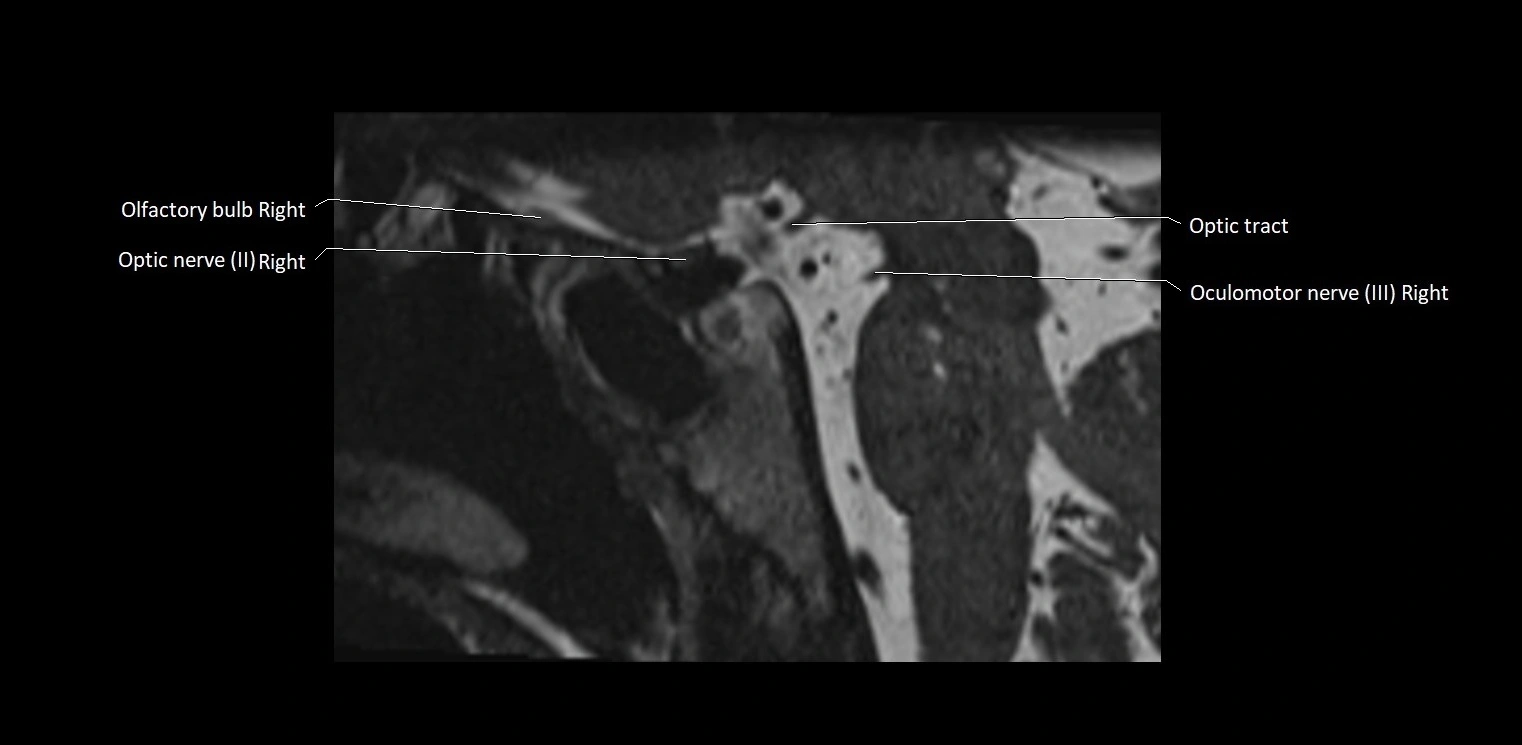

MRI Appearance

• The abducens nerve is a small, thin, linear structure

• Best visualized on high-resolution T2-weighted 3D MRI sequences (e.g., FIESTA or CISS)

• Seen as a hypointense (dark) line running from the brainstem at the pontomedullary junction, traversing the prepontine cistern, and entering Dorello’s canal under the petrosphenoidal ligament, then into the cavernous sinus, and finally the orbit

• May be challenging to visualize in standard MRI due to its small size

• Pathology may be inferred by absence, displacement, or enhancement of the nerve

MRI images

image